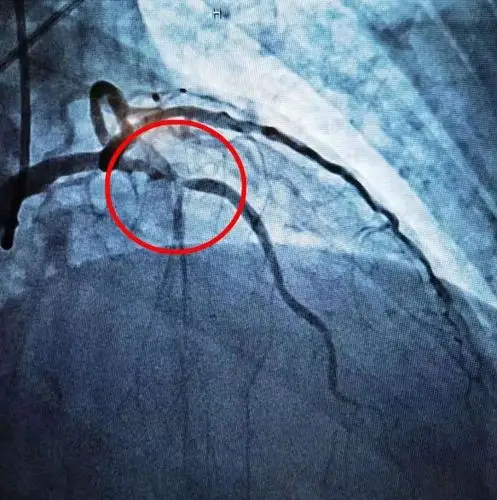

冠状动脉造影示前降支中段局限性狭窄约90%

"是冠状动脉造影,它是一种介入性的检查,能直观心脏血管狭窄的情况